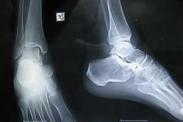

應力骨折是體育運動和軍事訓練中常見的損傷,屬于過度使用性損傷(overuse injury)的一種,亦稱疲勞骨折。與暴力引起的急性骨折不同,應力骨折是反復作用的閾下損傷積累的結果,其特征是骨的破壞和修復同時進行。